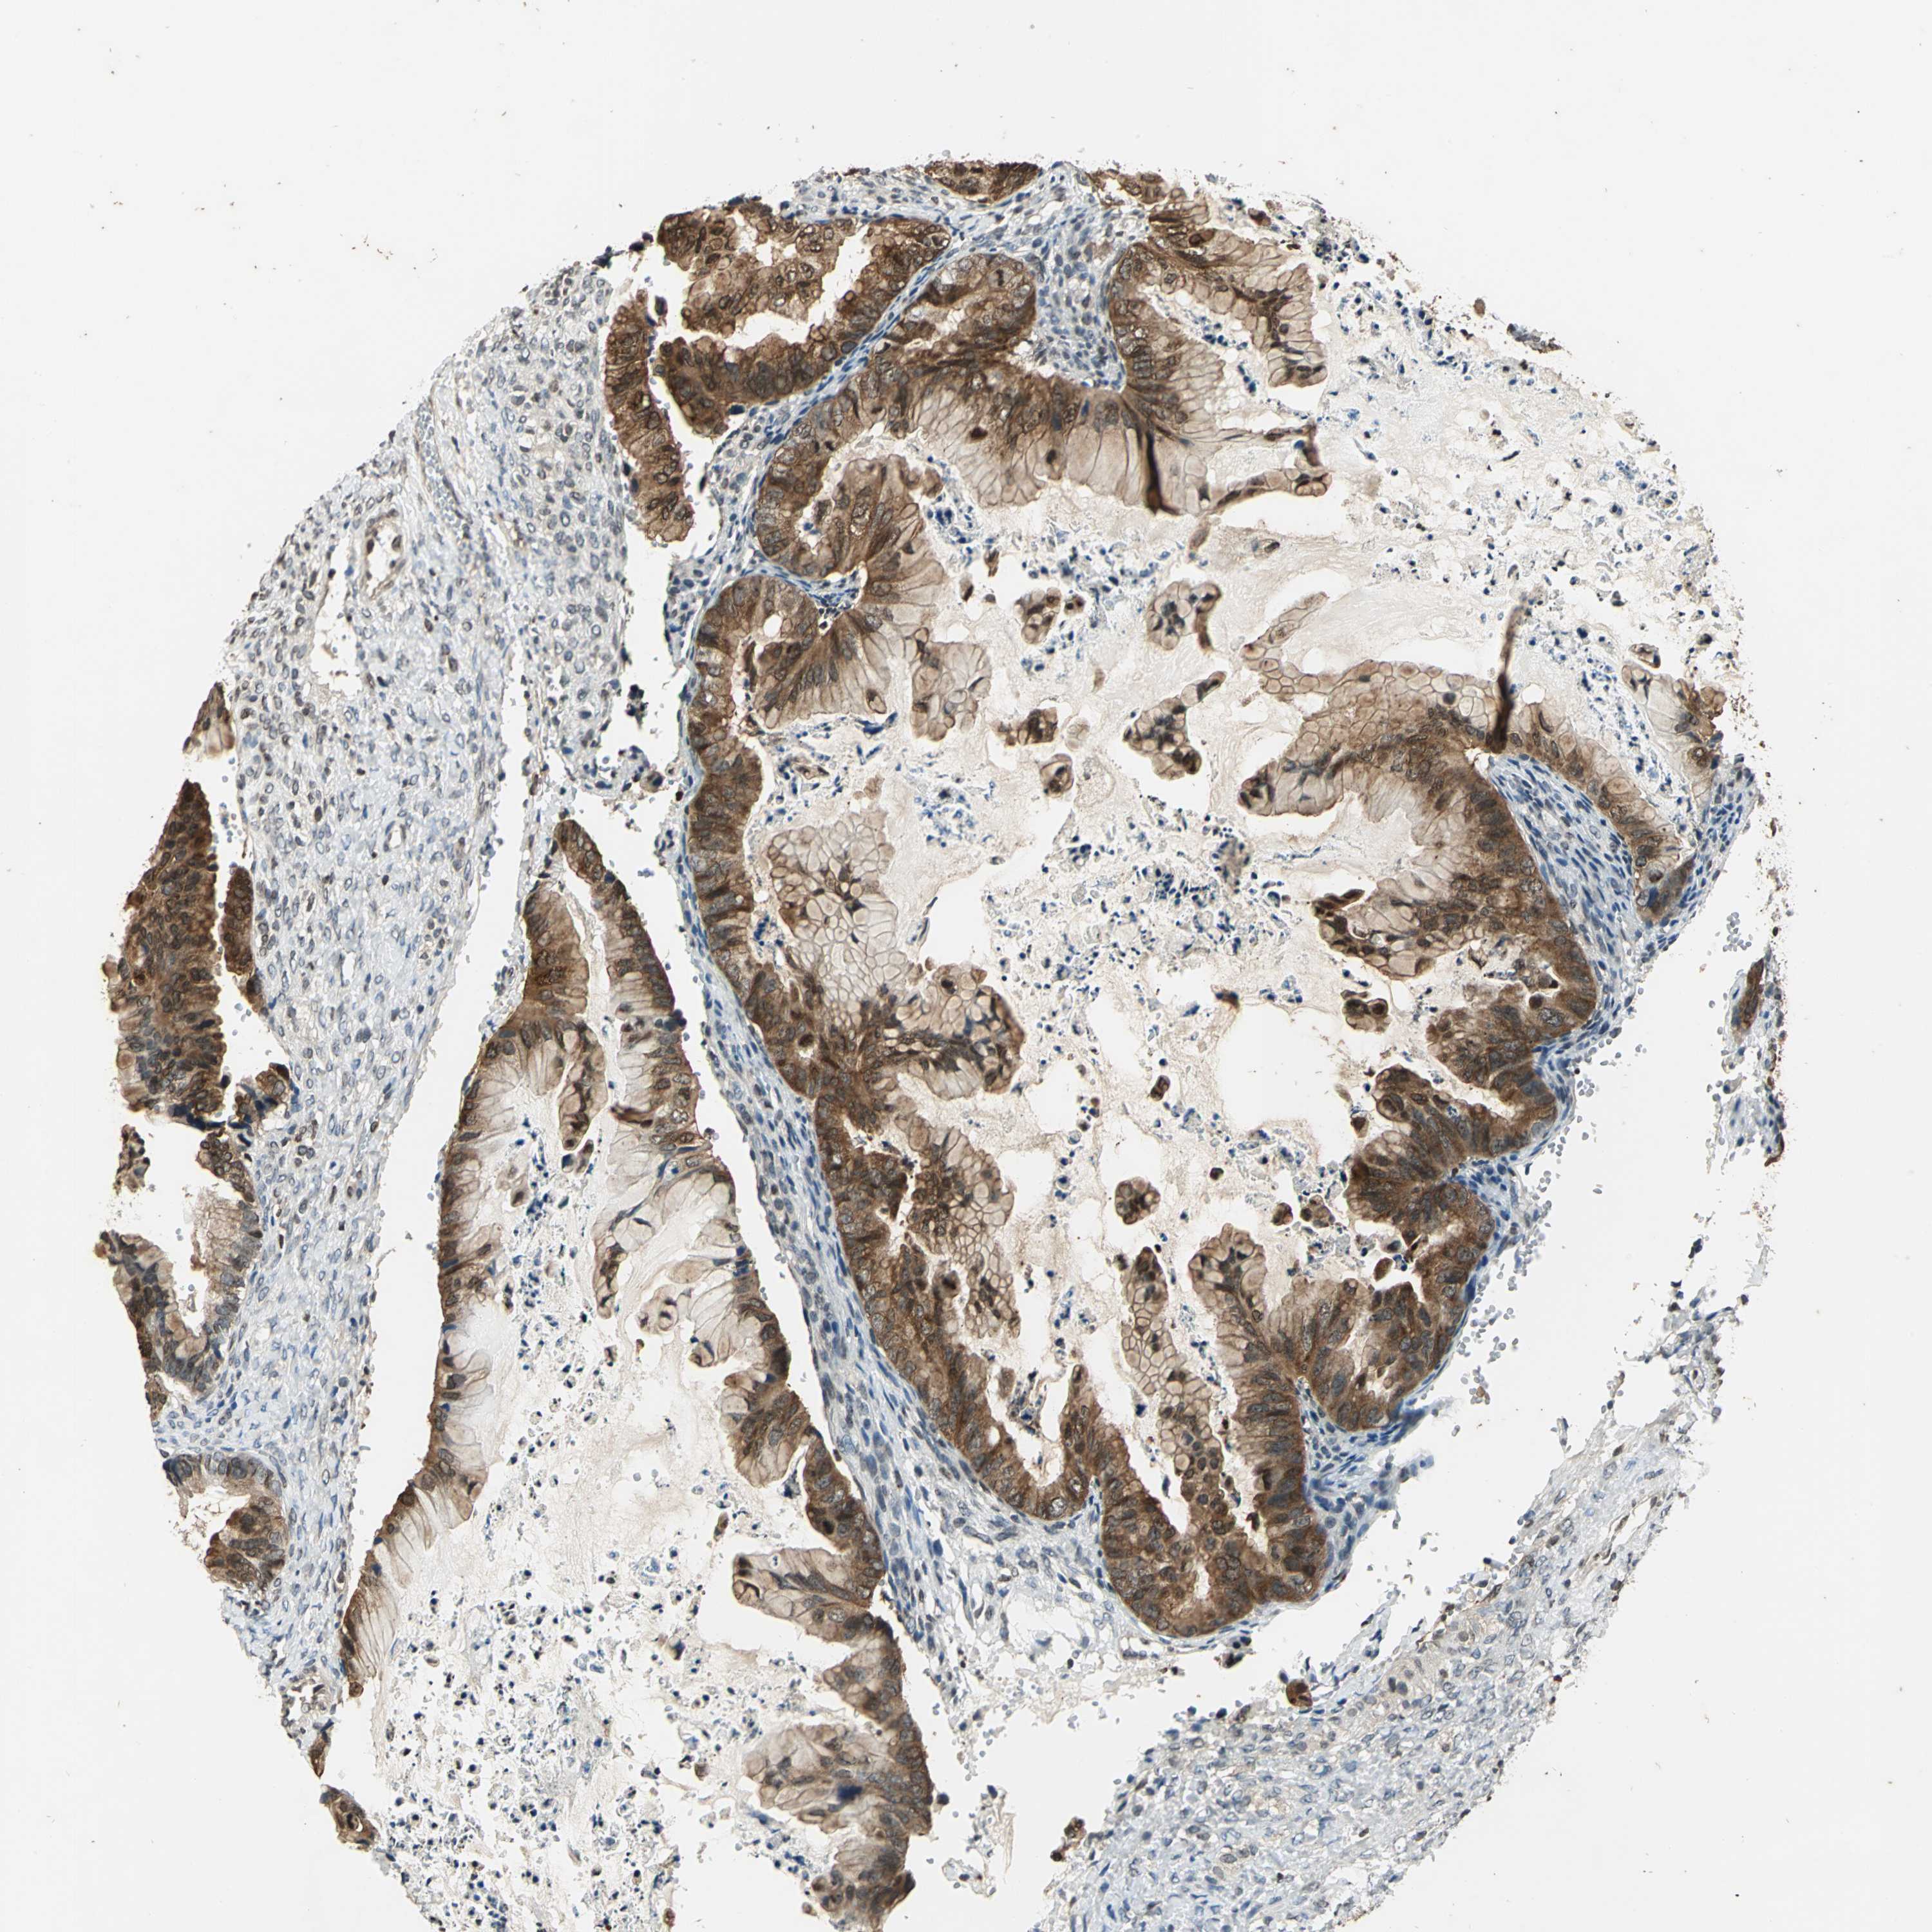

OVARIAN CANCER - Protein expressioni

A mouse-over function shows sample information and annotation data. Click on an image to view it in a full screen mode. Samples can be filtered based on level of antibody staining by selecting one or several of the following categories: high, medium, low and not detected. The assay and annotation is described here.

Note that samples used for immunohistochemistry by the Human Protein Atlas do not correspond to samples in the TCGA dataset.

Antibody stainingi

Antibody staining in the annotated cell types in the current human tissue is reported as not detected, low, medium, or high, based on conventional immunohistochemistry profiling in selected tissues. This score is based on the combination of the staining intensity and fraction of stained cells.

Each image is clickable and will lead to virtual microscopy that enables deeper exploration of all samples and also displays staining intensity scores, fraction scores and subcellular localization as well as patient and tissue information for each sample.

Antibody HPA003162

Antibody CAB005191

Staining

High

Medium

Low

Not detected

Intensity

Strong

Moderate

Weak

Negative

Quantity

>75%

75%-25%

<25%

None

Location

Nuclear

Cytoplasmic/membranous

Cytoplasmic/membranous,nuclear

Cystadenocarcinoma, mucinous, NOS

Carcinoma, endometroid

Cystadenocarcinoma, serous, NOS

Carcinoma, NOS